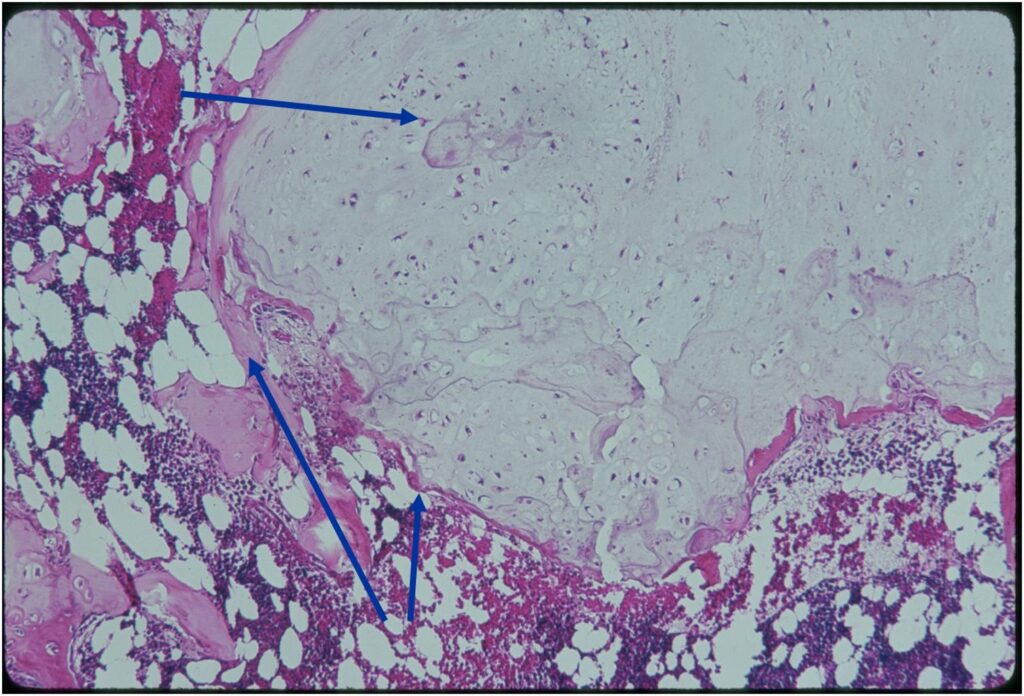

Microscopic Pathology

- Enchondromas are well defined lesions with cartilage arranged in lobules that are separated by fibrovascular septa

- Enchondral ossification may occur around periphery of lobules and when calcified appear as “Rings and Arcs” on X-rays

- Cells are in lacunae and have small dark nuclei

- Low cell count, cells appear bland with few chondrocytes and are similar size and shape

- There should never be any cortical destruction nor a soft tissue component. If this exists then the tumor must be a chondrosarcoma.

- Endosteal scalloping and cortical expansion is acceptable for phalangeal tumors. In most benign long bone cartilage tumors there is minimal endosteal scalloping but there should be no cortical expansion nor thickening. There should be no cortical destruction and no soft tissue component associated with an enchondroma. Cortical destruction, periosteal thickening, cortical expansion and a soft tissue component indicates a chondrosarcoma of the long bone.

- May cause mild expansile remodeling of bone and cortical thinning